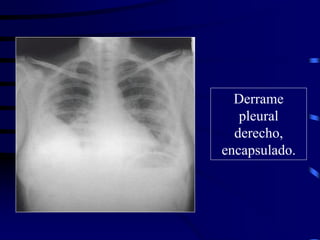

Derrame

pleural

derecho,

encapsulado.